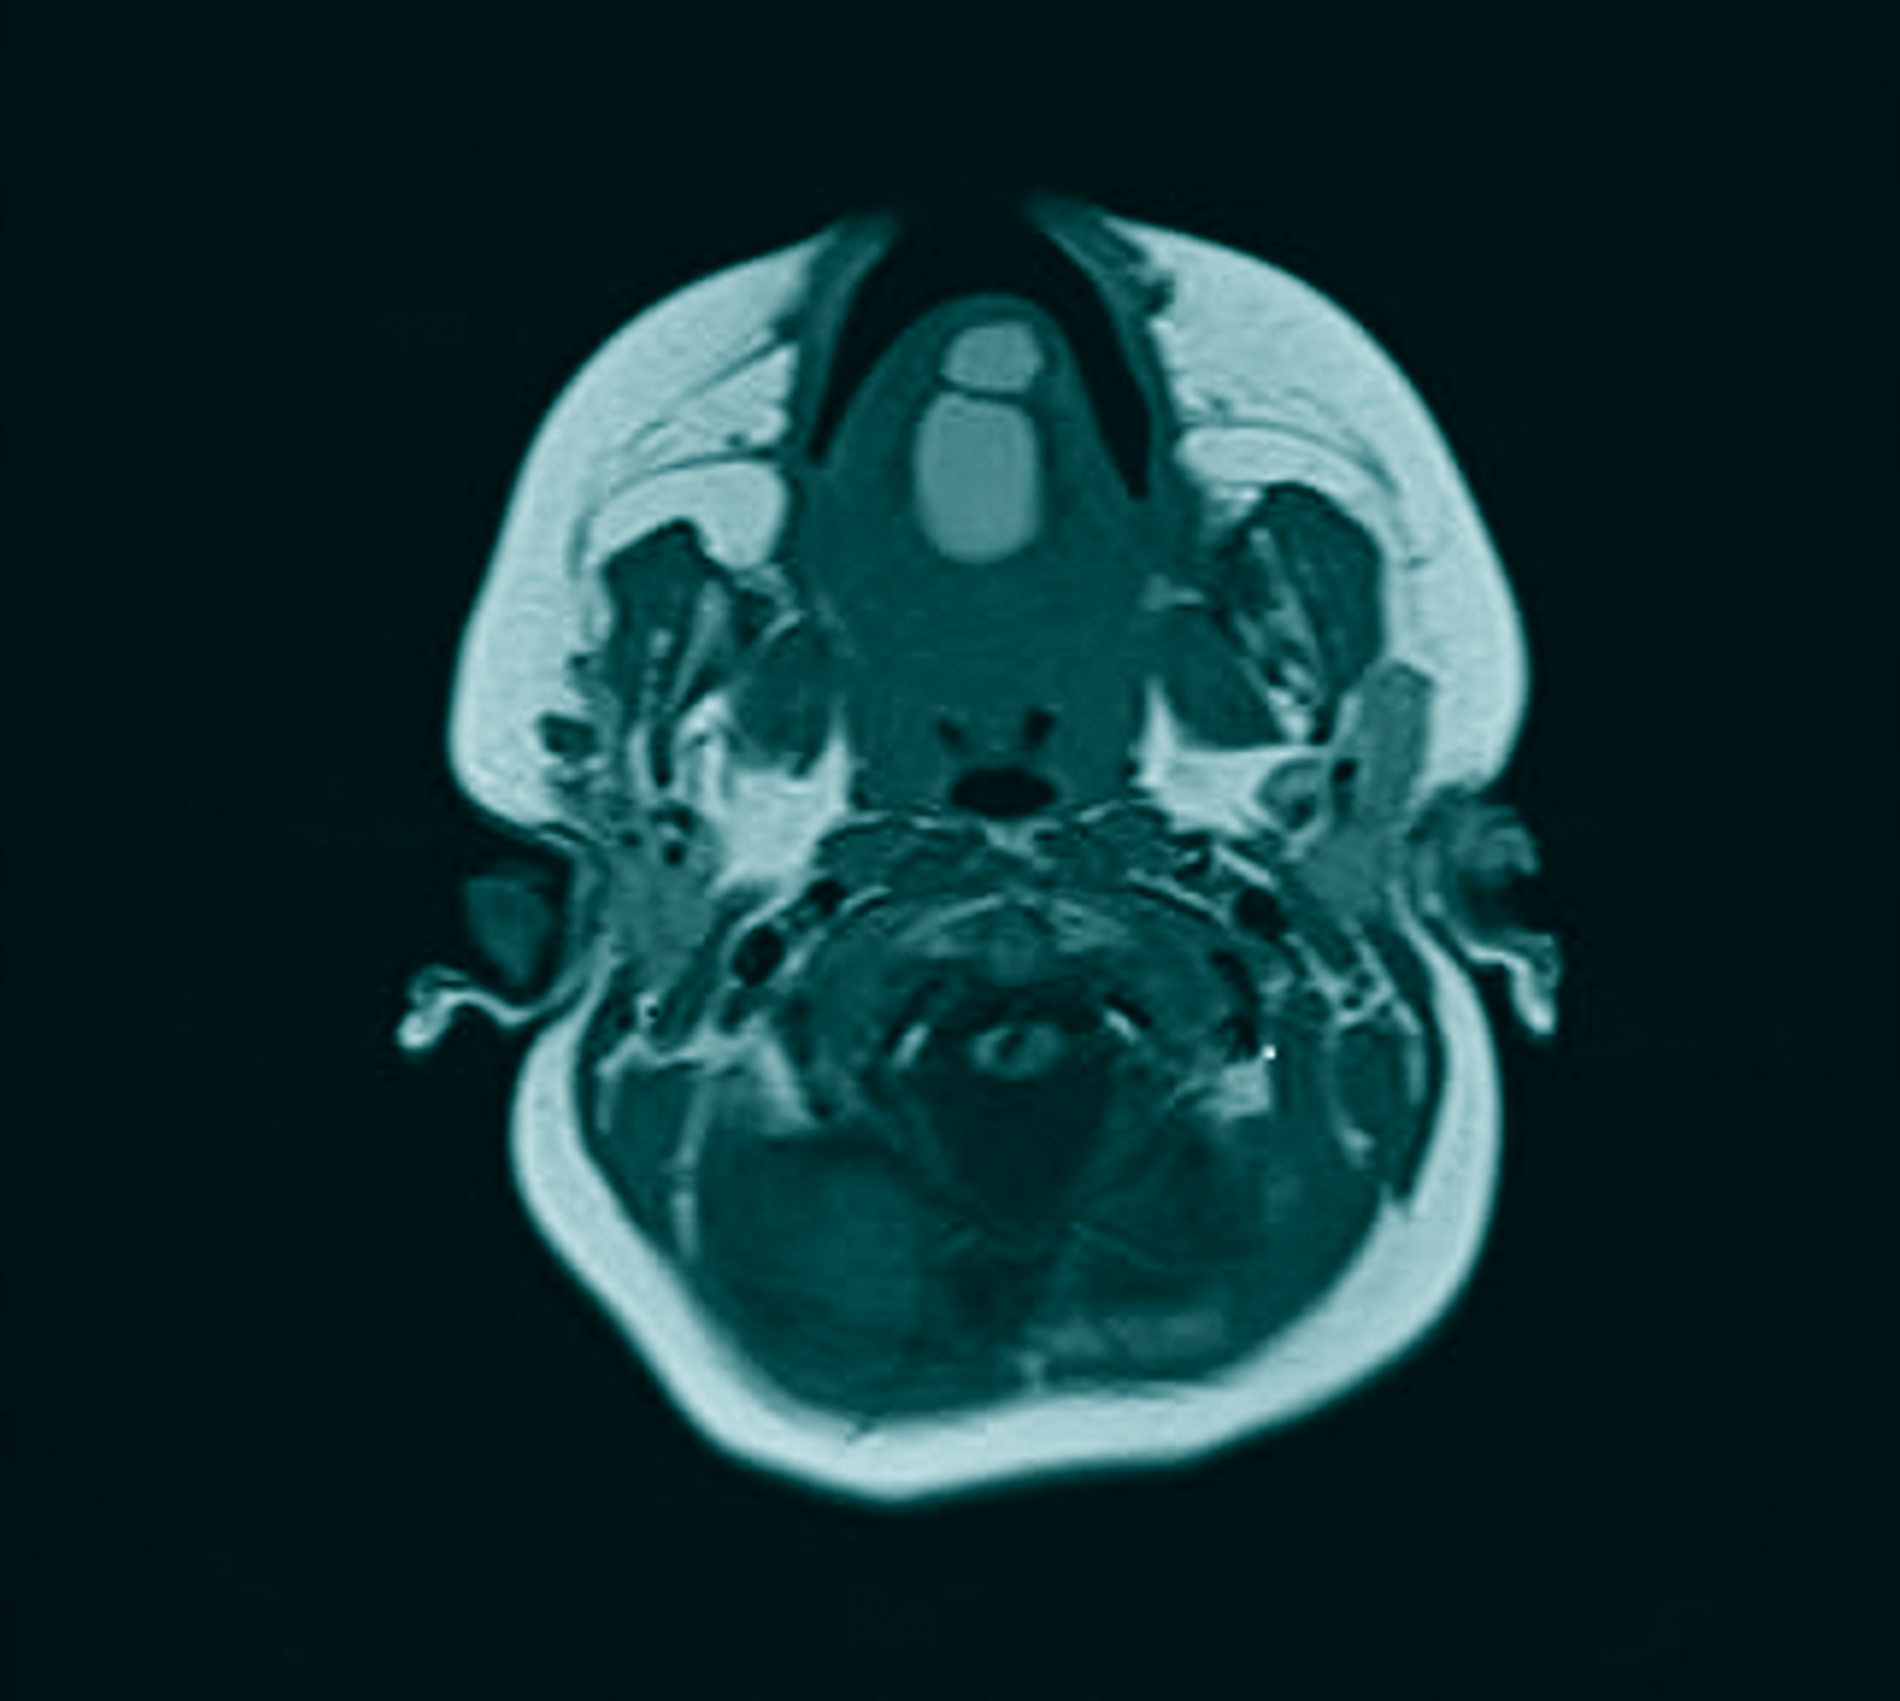

Zur erweiterten Diagnostik wurde in Sedierung eine Magnetresonanztomografie durchgeführt. Hier zeigten sich im Bereich des Zungenkörpers mit Übergang auf den Mundboden mehrere, konglomerierende zystische Läsionen (T1w nativ: flau hyperintense, Abbildung 2; T2w: hyperintense, teils diffusionsrestringiert, Abbildung 3) mit einer Gesamtausdehnung von 3,0 cm x 2,5 cm x 2,2 cm. Bildmorphologisch bestand der Verdacht auf eine Dermoid-Zyste, eine Foregut-Zyste oder ein zystisches Lymphangiom.